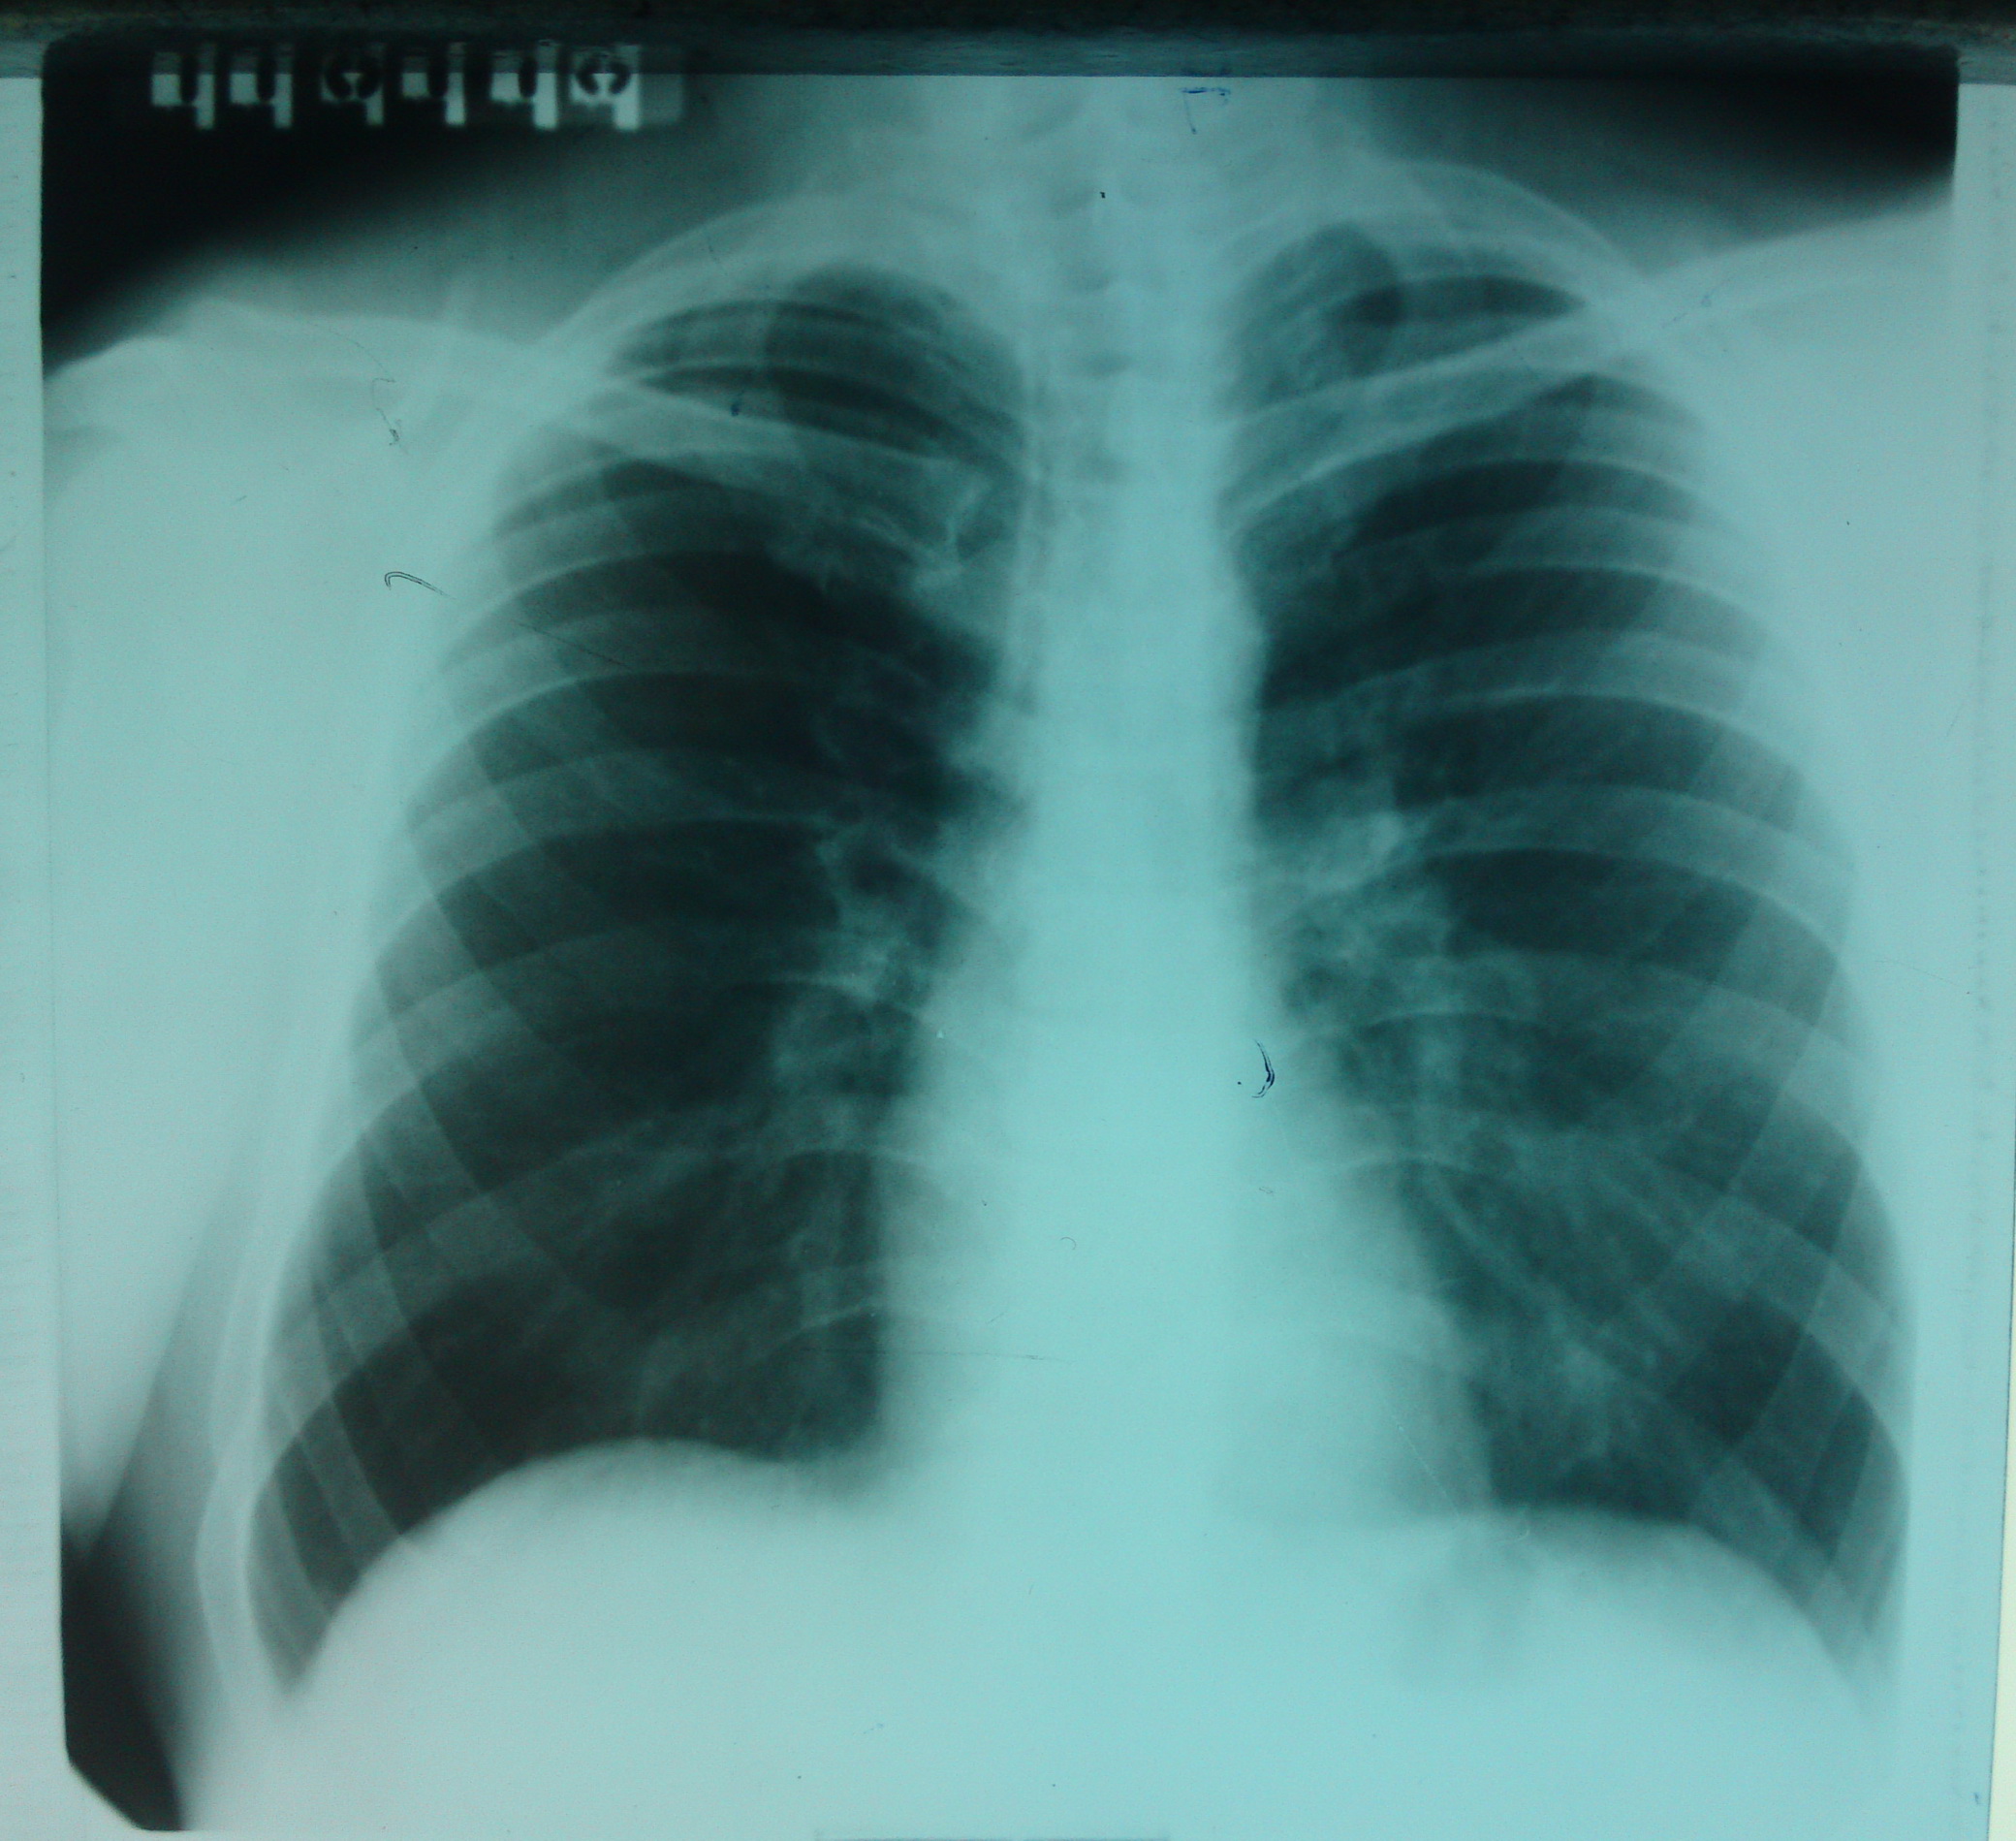

Мужчина, 42 года. Прошел флюорографию. Направлен на дообследование.

Предыдущая флюорография 11.01.10

Снимок после дообследования в прямой передней и левой боковой проекциях:

При беседе больной отмечает боли в левом плечевом суставе с иррадиацией в левую руку. Симптомов триады Горнера не отмечено (из беседы с участковым терапевтом).

С диагнозом Cr верхней доли левого легкого. Cr Пенкоста. направлен в онкодиспансер. Диагноз верифицирован. Стадия IV. Получает ХТ.